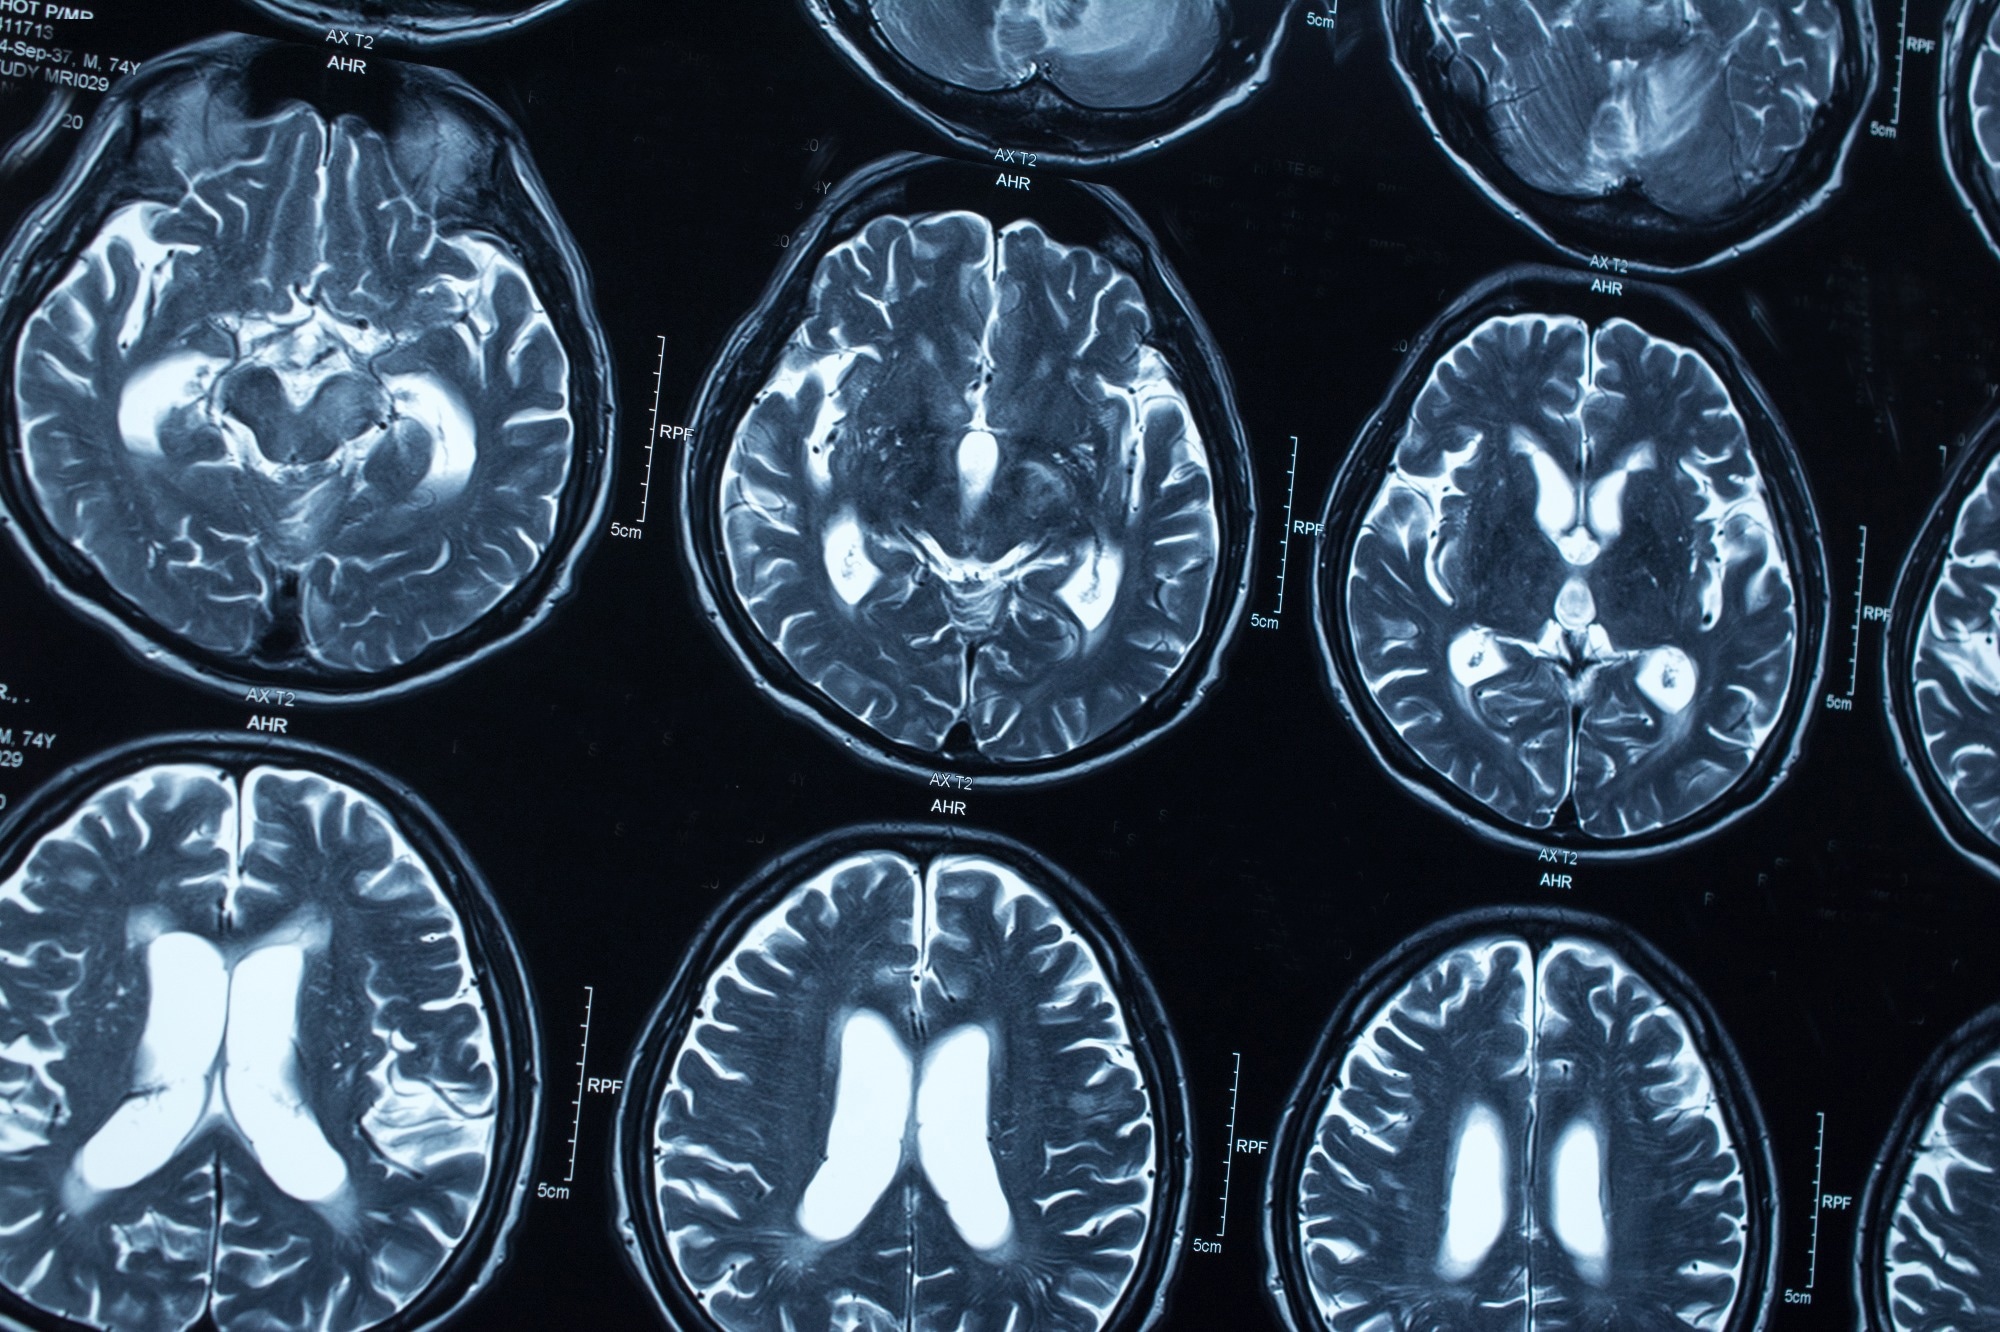

Study: Widespread transposable element dysregulation in human aging brains with Alzheimer's disease. Image Credit: Tushchakorn / Shutterstock.com